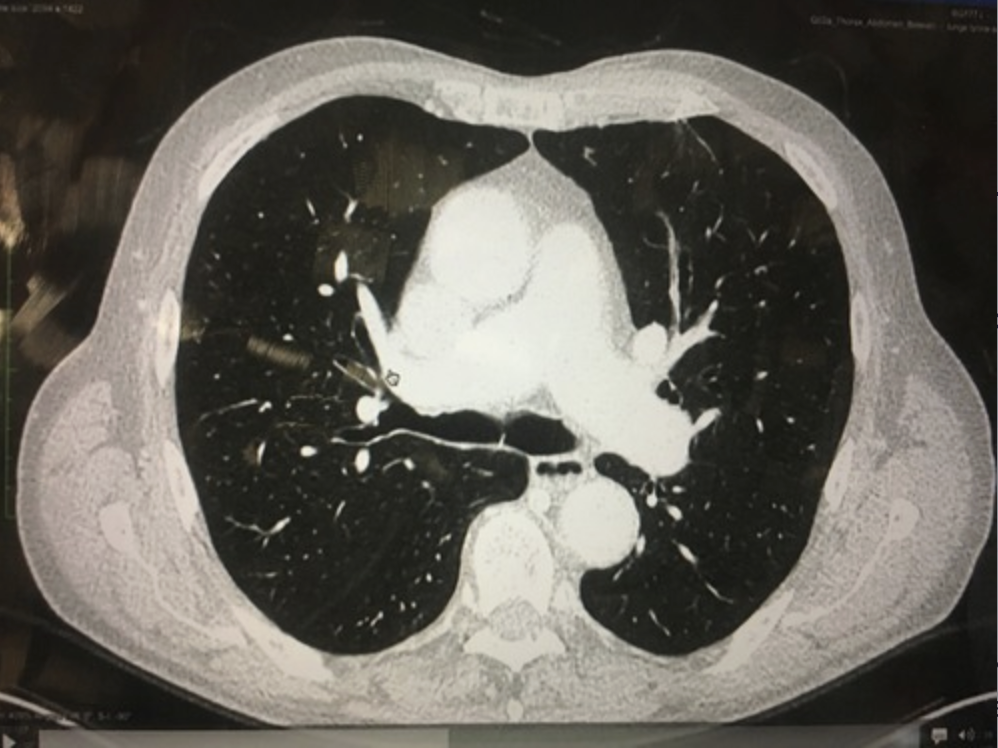

Elle passe à gauche, car le coeur est lui aussi à gauche

(Le boudin blanc sur la photo c’est la crosse aortique, la photo est prise par dessous, donc la gauche est à droite)